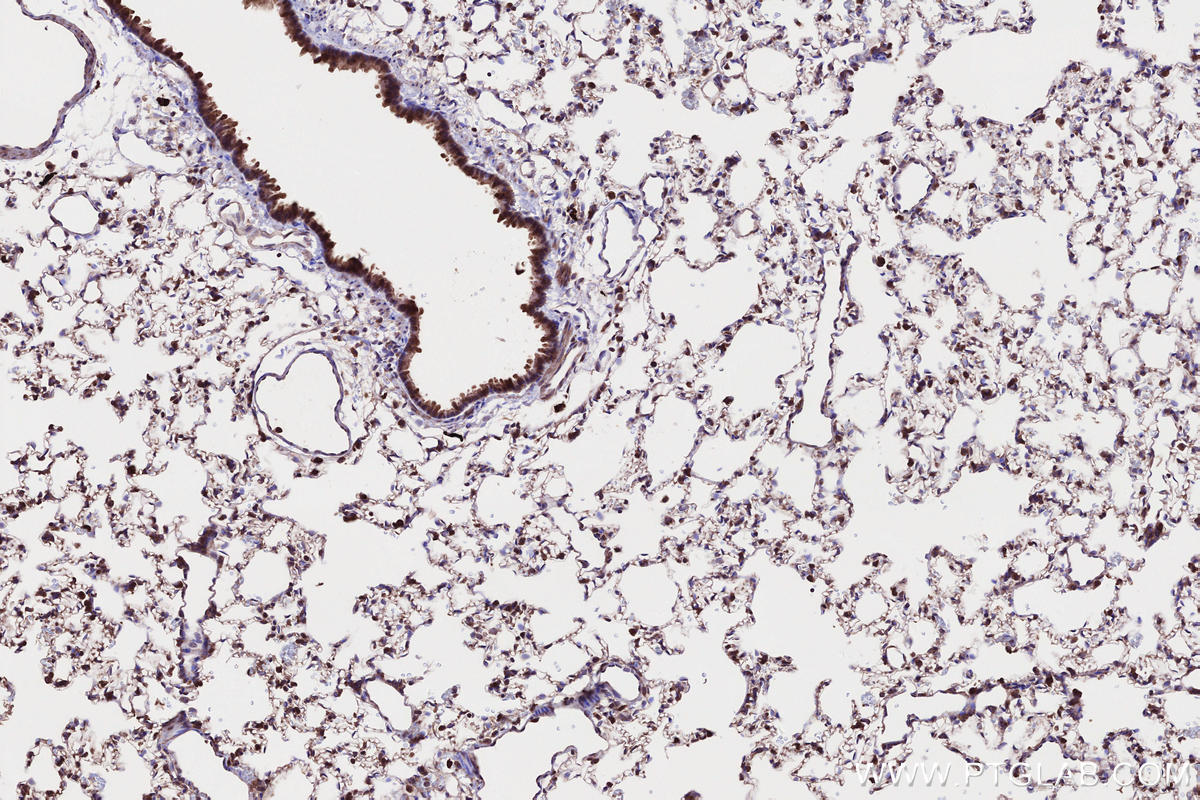

Validation Data Gallery